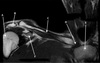

1

Q

What is letter A?

A

SUPRASPINATUS TENDON

What is letter B?

ACROMION